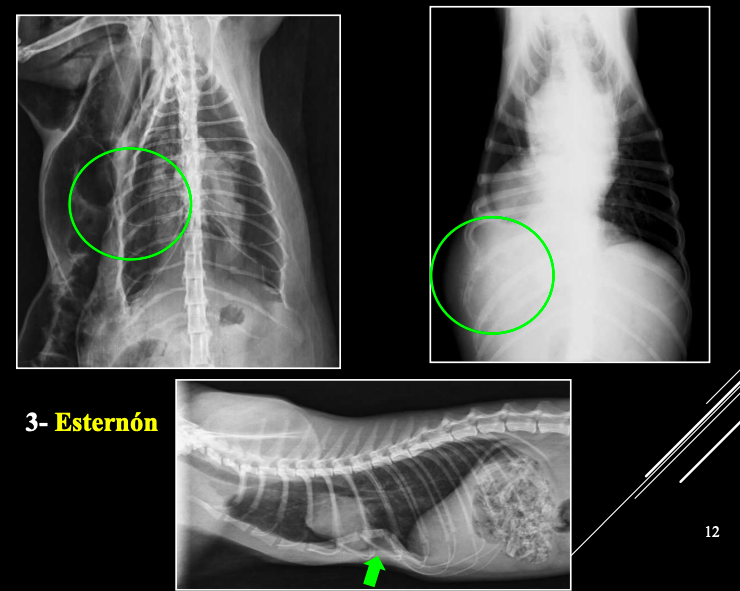

3. Esternón

- Escasas alteraciones significativas.

- Posibles: neoplasias, infección, pectus excavatum (Problemas aspiratorios, puede ser congenita) o pectus perinatum (poco frecuentes, perinatum aun menos)

Cosas que podemos ver:

- Engrosamientos

- Mineralizaciones

- extravasión de aire

- Masas (Dificil de decir si es hematoma, abceso, cuerpo extraño o neoplasia)

- Hipoplasia o aplasia de la decimotercera costilla.

- En geriatricos uniones condrocostales mineralizadas.(Formaciones en roseta)

- Fracturas

- Lisis osea por neoplasia o infección